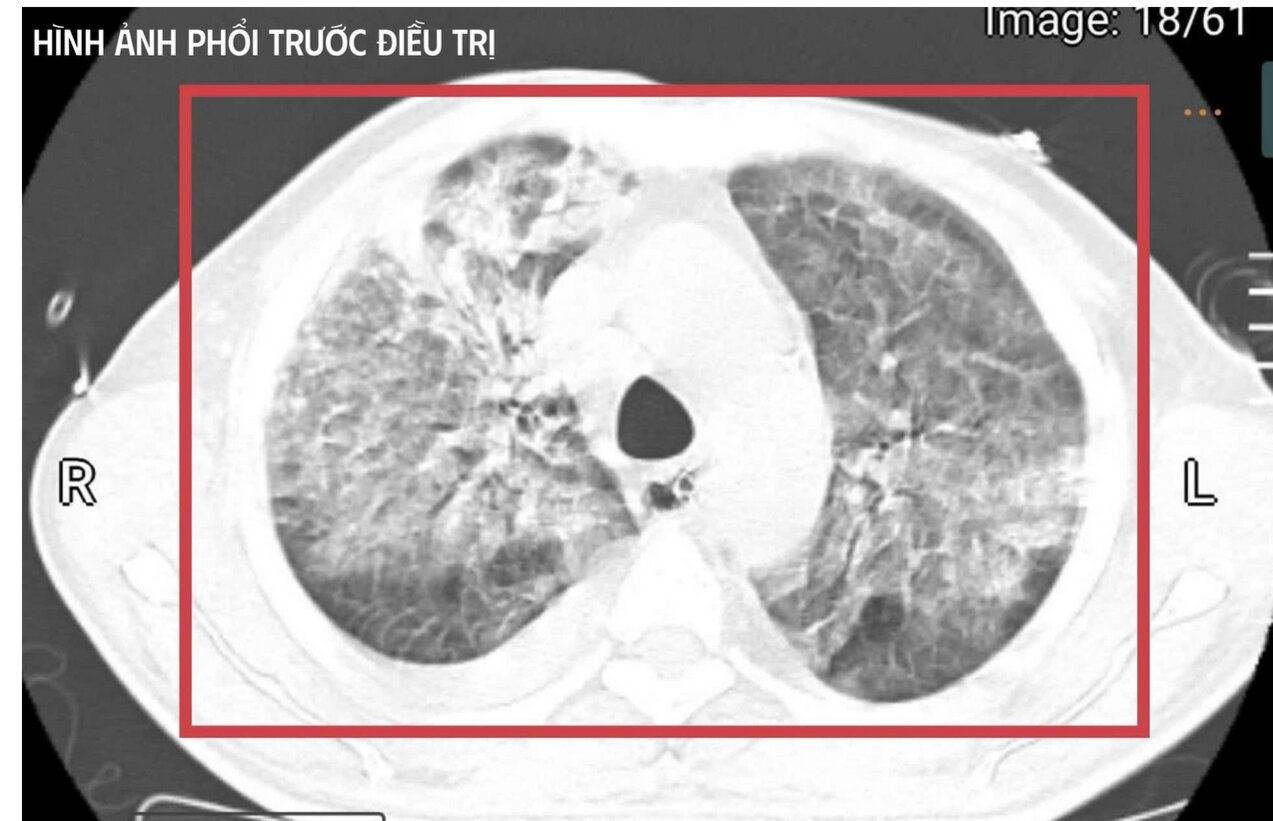

Bệnh nhân L.V.T (35 tuổi, Nghệ An) được đưa tới bệnh viện trong t́nh trạng nguy kịch. Bệnh nhân có tiền sử sinh sống và làm việc tại Thái Lan – khu vực lưu hành bệnh Whitmore cao.

Tại đây, bệnh nhân được đặt nội khí quản thở máy; kết quả cấy máu xác định nhiễm Burkholderia pseudomallei – tác nhân gây bệnh Whitmore. Dù được điều trị ban đầu, t́nh trạng vẫn diễn tiến nặng nên gia đ́nh xin chuyển bệnh nhân về Việt Nam để tiếp tục điều trị.

Nhiệt độ người bệnh liên tục 41–42°C kèm run cơ toàn thân, gợi ư t́nh trạng tăng thân nhiệt ác tính trên nền nhiễm khuẩn huyết tối cấp. Xét nghiệm cho thấy men gan và bilirubin tăng cao, rối loạn đông máu, creatinin tăng nhanh kèm vô niệu – biểu hiện của suy gan, suy thận cấp tiến triển.

Nồng độ CK vượt quá 100.000 U/l, kèm đau cơ và nước tiểu sẫm màu, phù hợp với tiêu cơ vân cấp . Các chỉ số viêm như CRP, PCT tăng rất cao, phản ánh t́nh trạng nhiễm trùng – nhiễm độc toàn thân dữ dội. Trên nền đó, bệnh nhân c̣n có đái tháo đường chưa kiểm soát và viêm gan C mạn, khiến cơ thể càng suy sụp.

Theo BS Kim Anh, đây là một trong những thể tối cấp của Whitmore – nhiễm khuẩn huyết nặng, suy đa tạng, rối loạn chuyển hoá sâu và có nguy cơ tử vong rất lớn trong thời gian ngắn nếu không được hồi sức tích cực ngay lập tức.

Đội ngũ bác sĩ phải "chạy song song" nhiều can thiệp: an thần sâu để kiểm soát kích thích và bảo vệ năo, hạ thân nhiệt chủ động nhằm khống chế tăng thân nhiệt ác tính, thiết lập đường truyền trung tâm, theo dơi huyết động liên tục, điều chỉnh toan–điện giải, phối hợp kháng sinh theo phác đồ điều trị Melioidosis và tiến hành lọc máu liên tục nhiều ngày để hỗ trợ chức năng thận, loại bỏ độc chất và giảm gánh nặng viêm.

Sau khoảng ba ngày hồi sức cao độ, bệnh nhân bắt đầu cắt sốt, các chỉ số viêm giảm dần, huyết áp ổn định hơn với nhu cầu vận mạch giảm, chức năng gan thận cải thiện, tri giác dần hồi phục. Người bệnh cai được thở máy qua mở khí quản, tập lại hô hấp tự nhiên và phục hồi vận động.